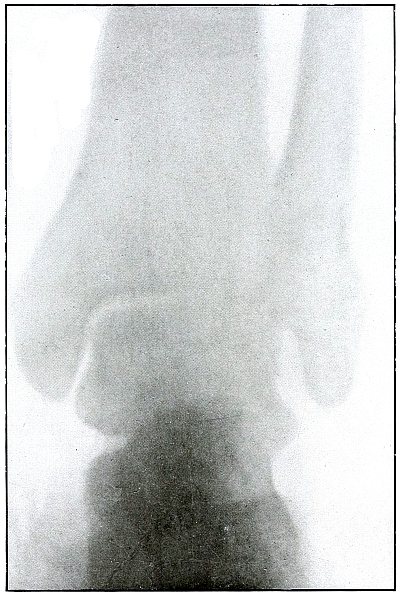

| 73. |

Gunshot wound, heel |

156 |

| 74. |

Gunshot wound, heel |

158 |